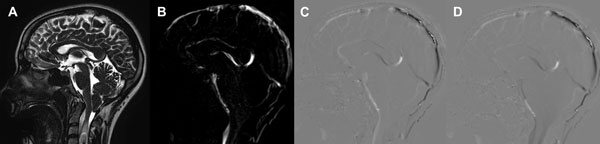

Estas secuencias permiten una evaluación cualitativa con valoración subjetiva del pasaje del LCR a través de las cisternas (Figura 1) y una valoración cuantitativa de la velocidad (Figura 2). La adquisición de las mismas se realiza de forma coordinada con el latido cardíaco (gatillado mediante el censado por el electrocardiograma o curva de pulso).13

Figura 1: Evaluación cualitativa en RM con técnica de contraste de fase. A: Imagen ponderada en T2 de alta resolución de cortes finos (3mm) que muestra el descenso amigdalino a través del foramen magno, el compromiso de las cisternas peritroncales y una siringomielia con imagen de turbulencia de flujo en su interior. B: Imagen en secuencia de fase que utiliza el contraste entre negro y blanco mostrando con señal hiperintensa el flujo de LCR cisternal C: Imagen de magnitud en fase anterógrada que muestra con señal hiperintensa el flujo en sístole. D: Imagen de magnitud en fase retrógrada que muestra con señal hipointensa el flujo en diástole. Con la valoración de estas secuencias en su totalidad y en reproducción en cine de las imágenes estáticas se logra la evaluación del pasaje de LCR a través de las cisternas peritroncales y los forámenes del cuarto ventrículo.